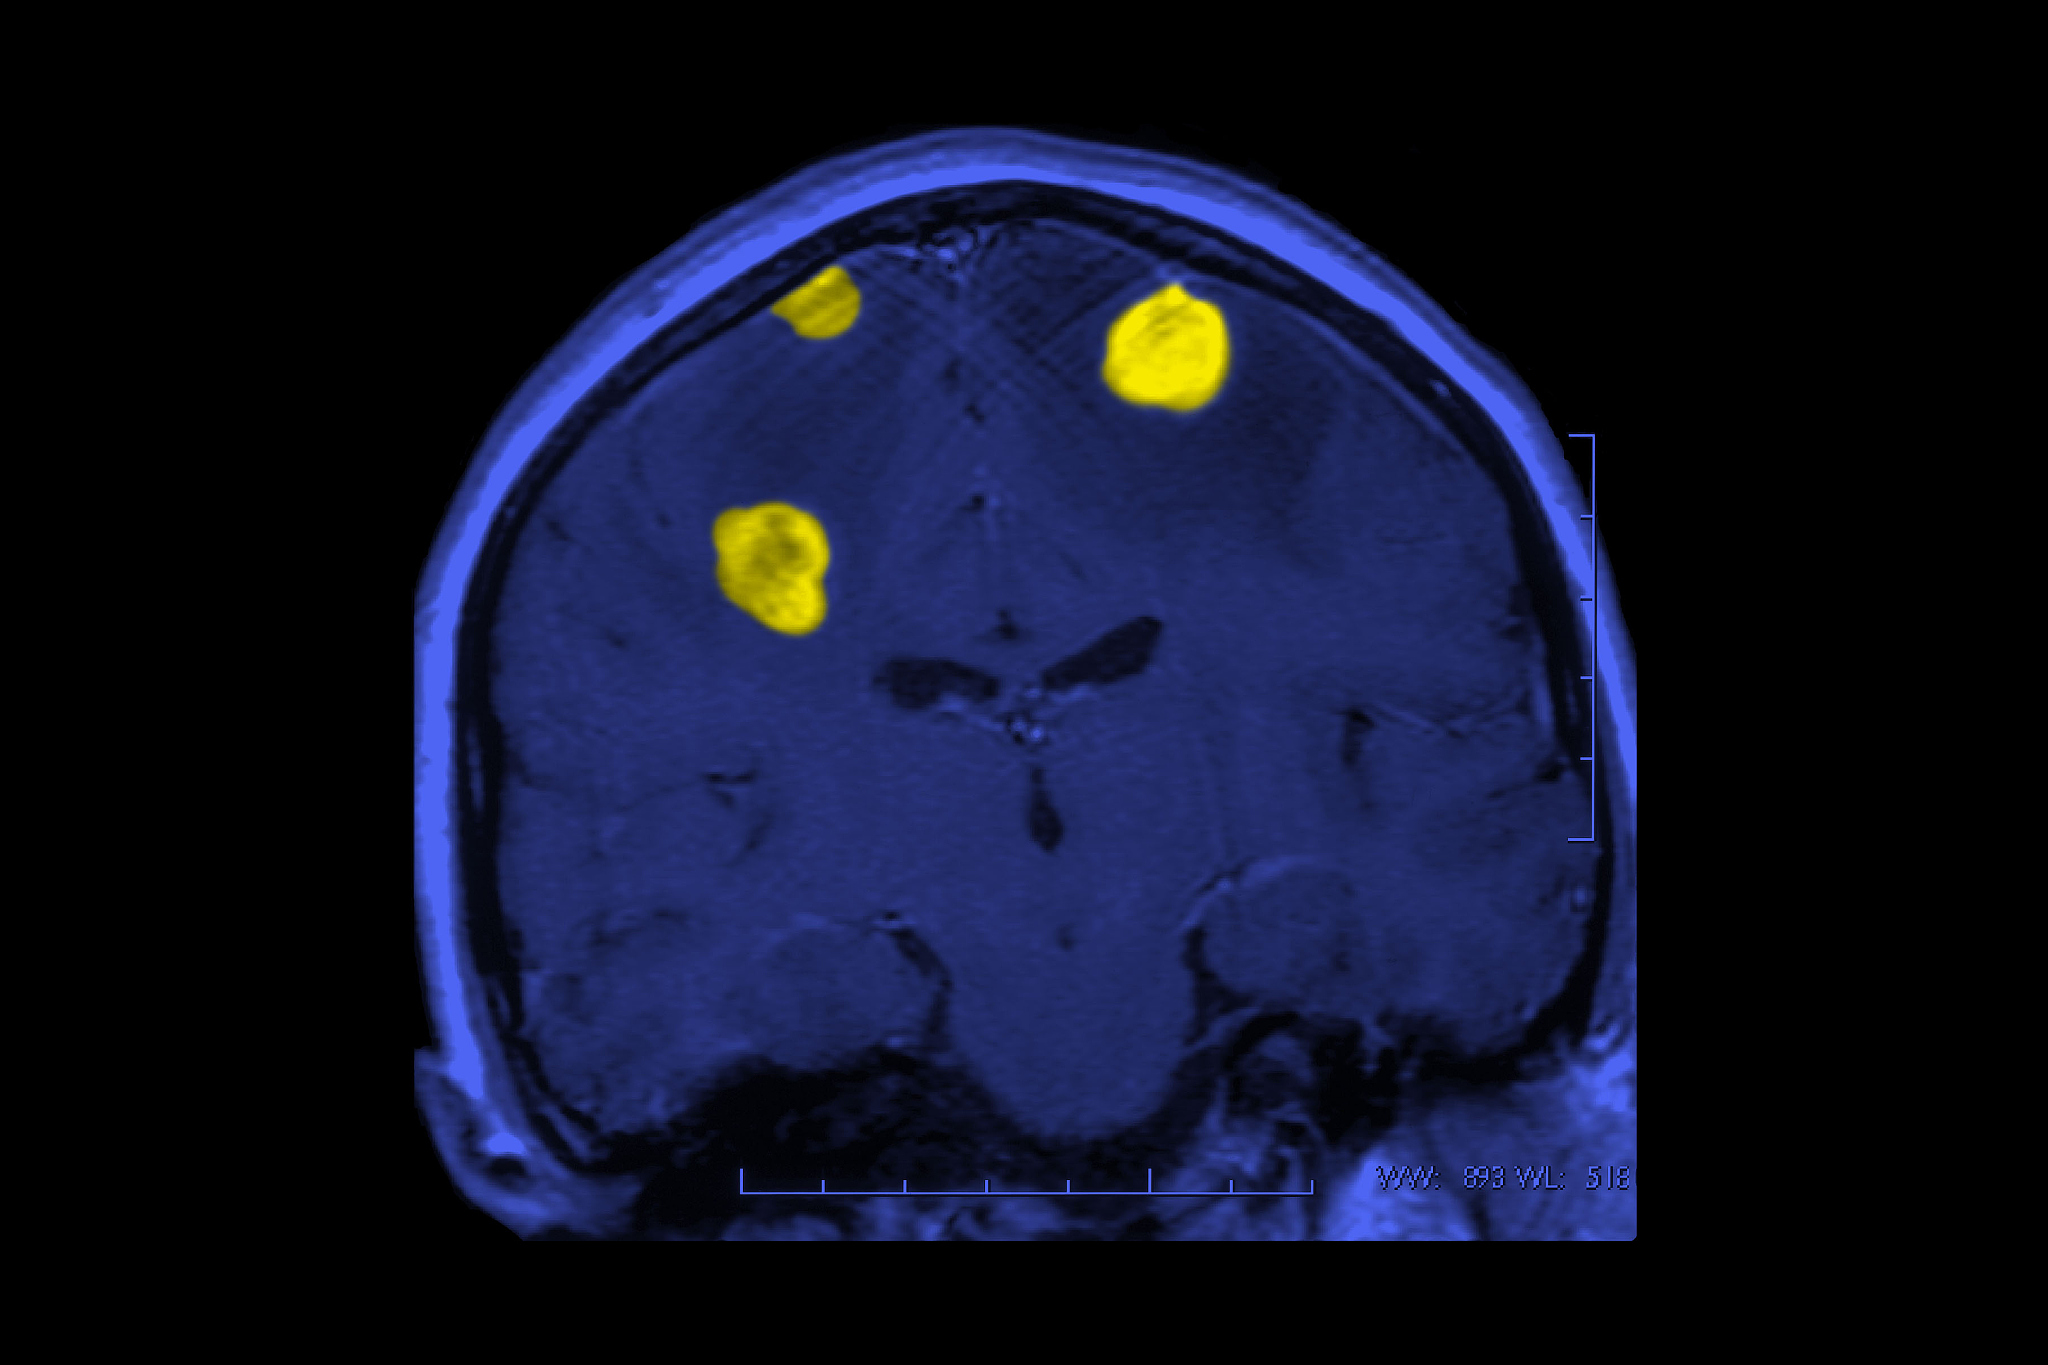

高内涵细胞成像技术可以通过同时测量多个生物学参数,包括细胞形态学、蛋白质表达、基因表达等,来检测细胞的上皮质转化作用。例如,可以通过测量细胞的形态学特征,如细胞大小、形状和核形态等,来检测细胞的上皮质转化程度。此外,还可以通过测量细胞中特定蛋白质的表达水平来评估细胞的上皮质转化程度。例如,上皮细胞中常见的蛋白质E-细胞粘附分子(E-cadherin)可以通过高内涵细胞成像技术来测量其表达水平,从而评估细胞的上皮质转化程度。

高内涵细胞成像技术在肺癌上皮质转化作用的检测中有广泛的应用。该技术可以在肺癌组织中检测上皮质转化的程度,并评估患者的肿瘤发展和预后。此外,该技术还可以在肺癌细胞模型中研究上皮质转化的机制和调控因素,为肺癌的治疗提供新的靶点和策略。